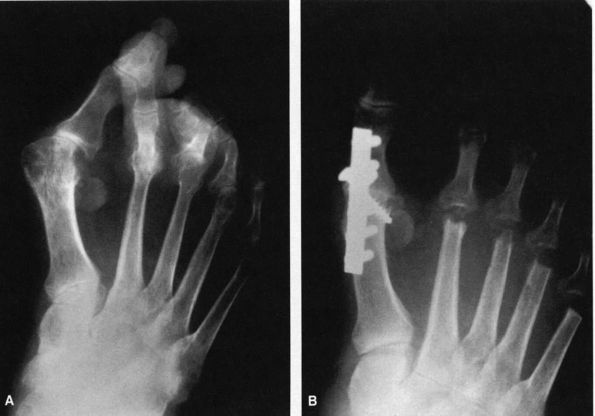

![]() |

FIGURE 21-3. Radiographic observations of the hallux valgus deformity. (A) Hallux valgus angle: normal (less than 15°). Intermetatarsal angle: normal (less than 9°). (B) Distal metatarsal articular angle (DMAA): normal (less than 10° lateral deviation). (C) Marked obliquity of the metatarsocuneiform joint should alert clinician to possible instability of this joint. (D)

A congruent joint is one in which there is no lateral subluxation of the proximal phalanx on the articular surface of the metatarsal head. (E) The incongruent or subluxated joint has lateral deviation of the proximal phalanx on the metatarsal head. |

The intermetatarsal angle formed by the axes of the first and second metatarsals on the AP view.

The hallux valgus angle formed by the axes of the first metatarsal and the proximal phalanx of the hallux.

The congruity of the joint. In other

words, does the articular surface of the proximal phalanx line up with

that of the metatarsal head or is it subluxated? -

The distal metatarsal articular angle

formed by the alignment of the first metatarsal and the margins of the

joint surface of the first MTP. -